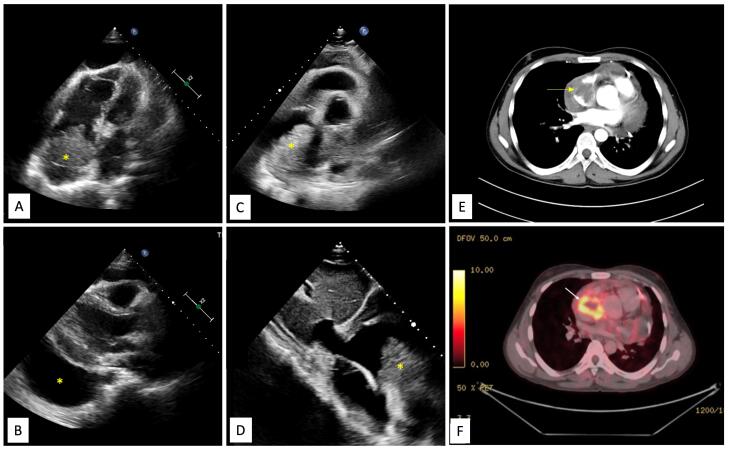

一位28岁男性,有较短的进行性呼吸困难病史,心包大量积液伴心包填塞,超声心动图检查发现右心房有心内肿块。多模态影像显示不规则肿块邻近RA外侧壁,浸润周围心包及上腔静脉。正电子发射断层扫描(PET)证实肿块为代谢活跃病变,并伴有纵隔结构和淋巴结的摄取。经皮心肌膜活检无效后,行开放性手术活检。组织学检查证实为心脏血管肉瘤。不幸的是,患者在活检后出现难治性休克和复发性大量心包积液(出血性)而死亡。该病例强调了结核流行地区心包积液的诊断困境,多模态成像在确认心脏恶性肿瘤中的作用以及此类患者的不良预后。

A 28-year-old male with a relatively short history of progressive dyspnea and a large pericardial effusion with tamponade was found to have an intracardiac mass localized in right atrium (RA) on echocardiography. Multimodality imaging revealed an irregular mass abutting the lateral wall of RA, with infiltration into surrounding pericardium and superior venacava. Positron emission tomography (PET) scan confirmed the mass as metabolically active lesion, along with uptake in mediastinal structures and lymph nodes. After an unrewarding percutaneous endomyocardial biopsy, open surgical biopsy was performed. Histologic examination confirmed the diagnosis of cardiac angiosarcoma. Unfortunately, patient had refractory shock and recurrent massive pericardial effusion (hemorrhagic) after biopsy and succumbed. The case highlights diagnostic dilemma of pericardial effusion in tuberculosis-endemic areas, role of multi-modality imaging in confirming cardiac malignancy and poor outcome of such patients.